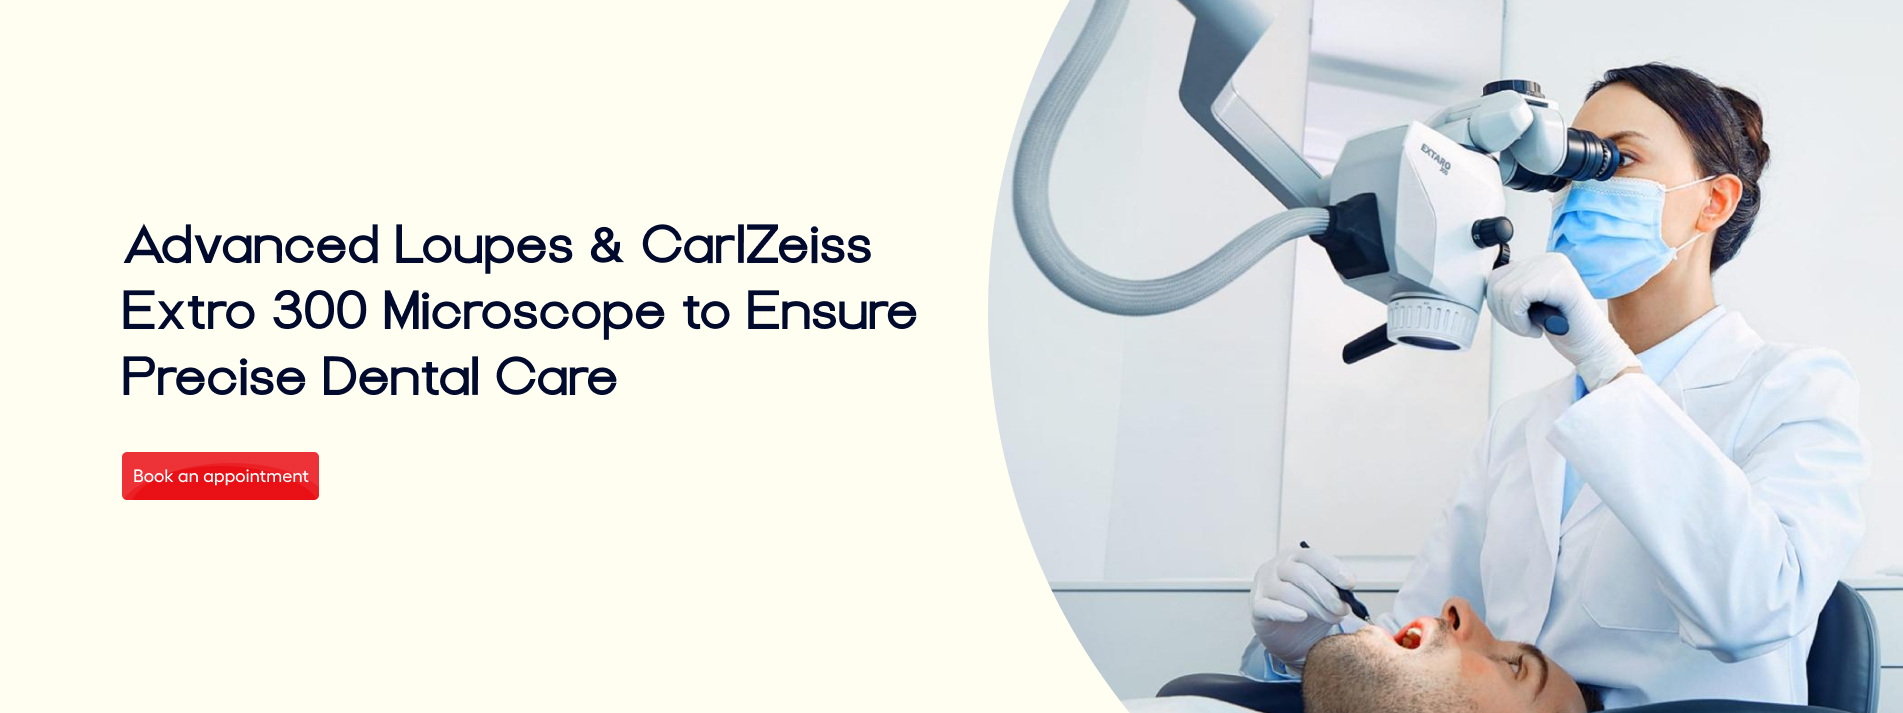

Expert Care

Our dedicated team of skilled dentist, consultants and lab technicians is committed to providing exceptional multi-disciplinary treatment under a singlr roof. We prioritize your comfort and satisfaction, ensuring you leave with a smile.

From routine cleanings and preventive care to advanced cosmetic and restorative dentistry, we offer a full range of dental services to keep your smile healthy and vibrant.

Comfortable Environment

Our modern, state-of-the-art facility is designed with your comfort in mind. We strive to create a relaxing atmosphere where you feel at ease throughout your dental visit.